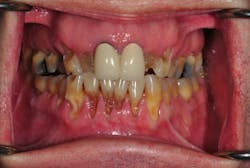

A thorough clinical examination designed to discover both functional and biological problems is critical to this approach. Through the exam, we are able to:

- Determine the health and position of the temporomandibular joints,

- Check the muscles of mastication for symptoms of disharmony, and

- Look for any signs of occlusal instability (wear, mobility, and migration).

Before we start prepping teeth, we have to be certain that our foundation is sound, which means establishing biologic health, including addressing periodontal concerns and caries control.